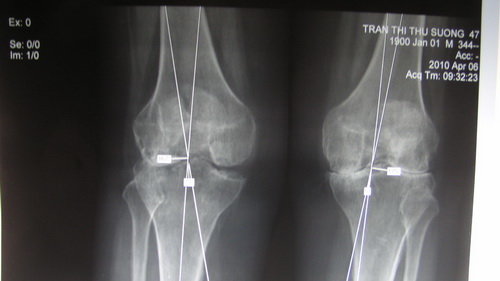

| Hình hư khớp gối trên bệnh nhân đã được chẩn đoán viêm khớp dạng thấp. Ảnh: BS Nam Anh |

Viêm khớp thấp khởi đầu là bệnh lý của viêm bao khớp nhất là lớp lót bên trong làm tăng tiết dịch gây sưng to khớp. Dịch tiết ra lâu dần gây hủy hoại mặt sụn và làm hư biến khớp khiến cho việc đi lại sẽ khó khăn. Bệnh có thể diễn tiến từng đợt.